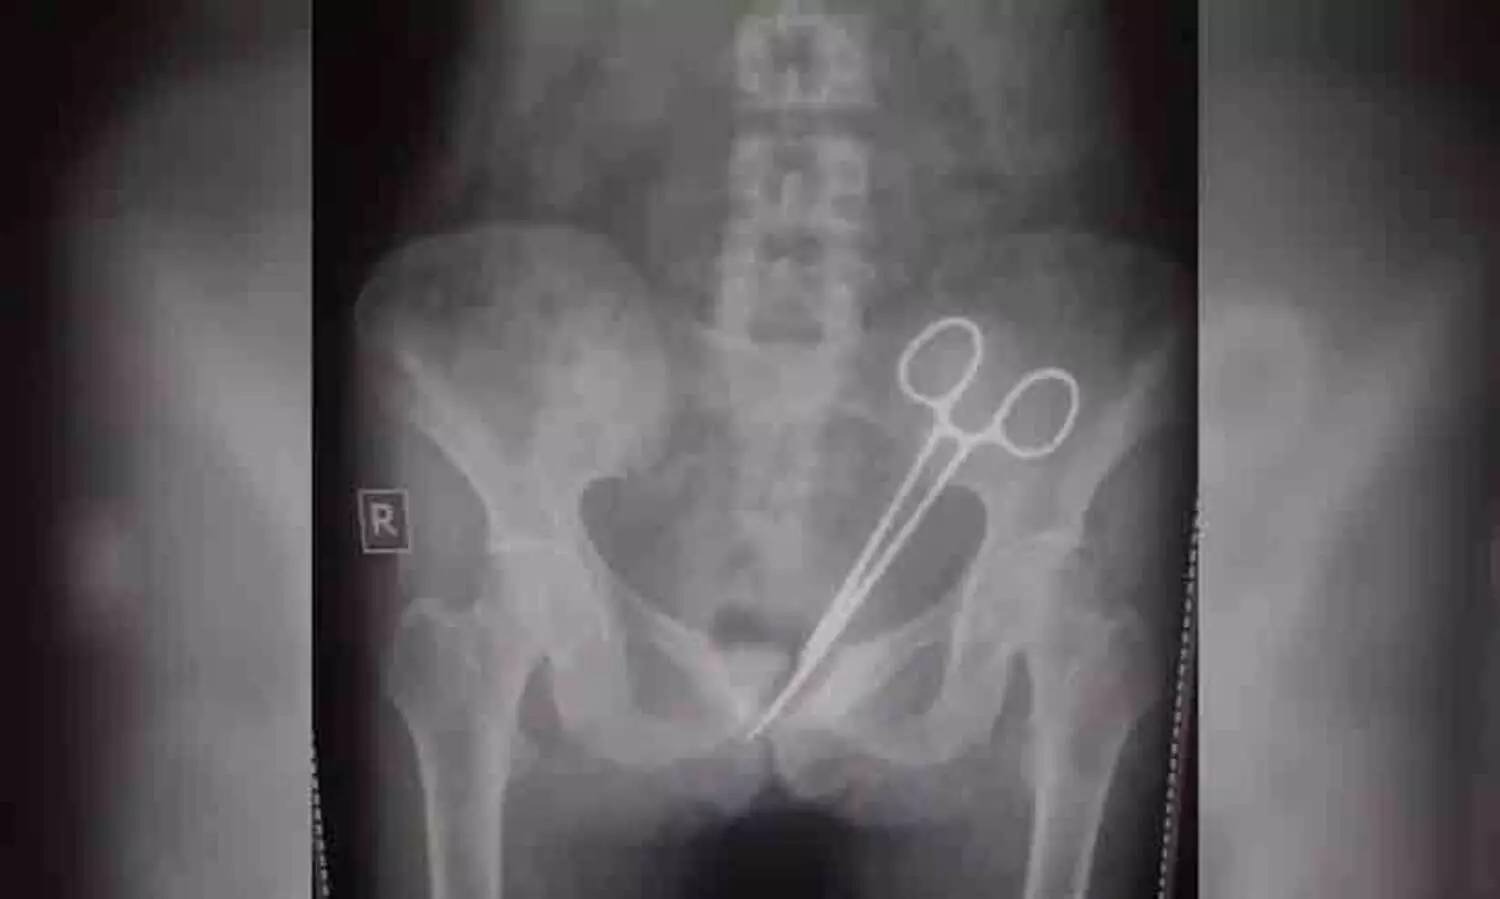

ശസ്ത്രക്രിയക്കിടെ ഡോക്ടർമാർ യുവതിയുടെ വയറ്റിൽ വെച്ചു മറന്ന കത്രിക കണ്ടെത്തി; 12 വർഷത്തിനു ശേഷം